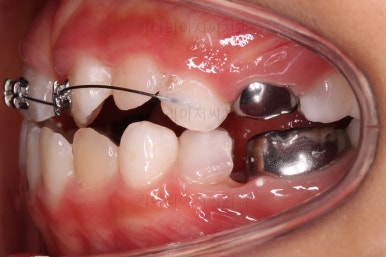

부산어린이반대교합 초진 시, 치열의 모습이에요.

우선 유치들이 많이 썩어서 치료가 필요해 보였고요.

앞니가 거꾸로 물려있고(아래 앞니가 위 앞니보다 앞으로 튀어나간 상황) 삐뚤어 있어요.

부산어린이반대교합 이번에 사용한 장치는 메탈 브라켓이며 테크닉적으로는 투 바이 포 교정이라고 합니다.(2x4)

삐뚤어진 앞니를 가지런히 하면서 아랫니 보다 뒤에 있는 윗니의 위치를 바로 잡아 주는거죠.